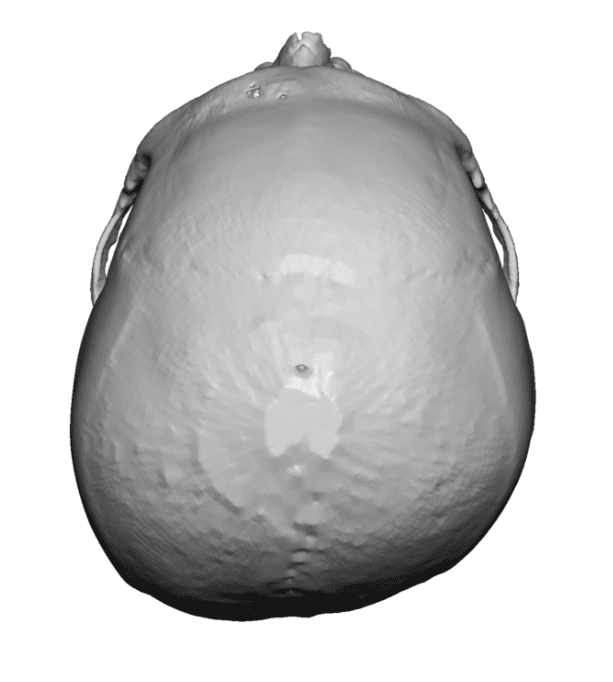

Desire to build up the flatter upper part of the back of his head.

Upper occipital skull augmentation using a custom skull implant.

Desire to build up the flatter upper part of the back of his head.

Upper occipital skull augmentation using a custom skull implant.